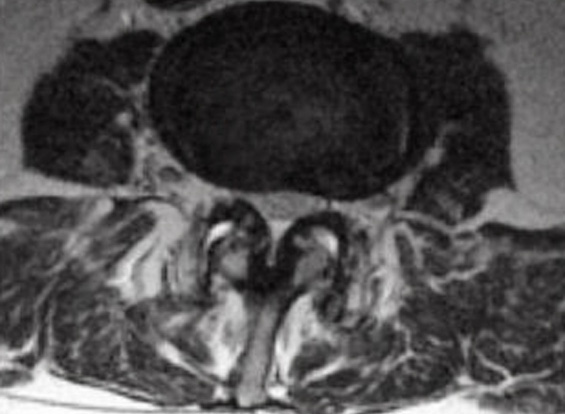

These changes showed advancement of his disease since prior imaging in 2008. The patient was evaluated by neurosurgery at the time of imaging and was determined to have neurogenic claudication with bilateral L5 radiculopathies with severe L4-L5 central and foraminal spinal stenosis and grade 1 spondylolisthesis (refer to Figures 1 and 2).

Figure 2. Axial magnetic resonance imaging (MRI) demonstrating severe central spinal stenosis.